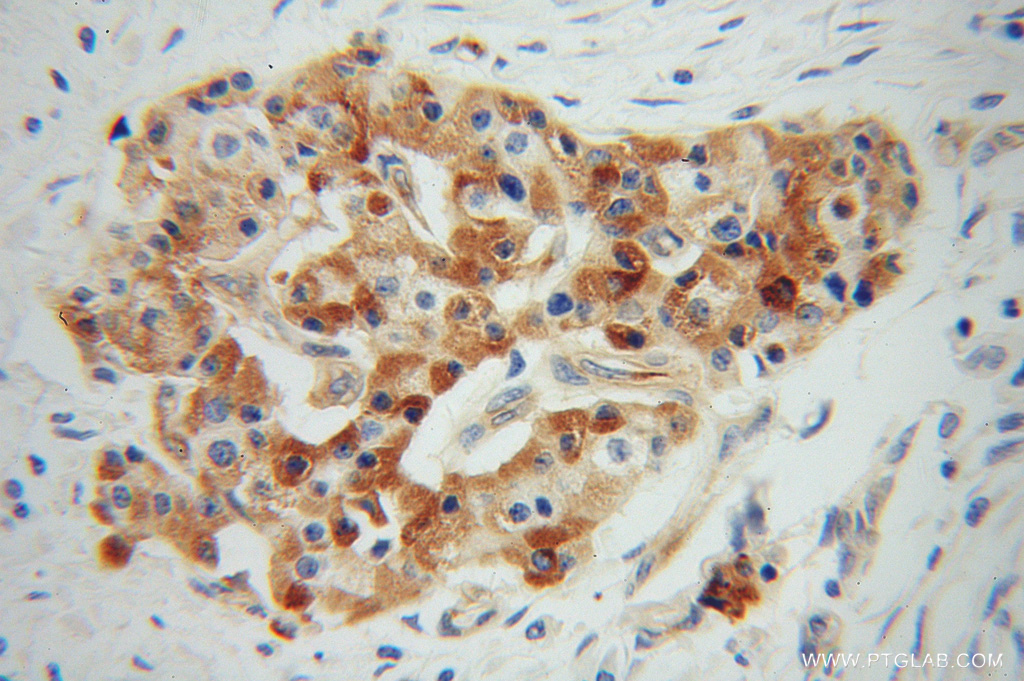

| Positive IHC detected in | human pancreas cancer tissue Note: suggested antigen retrieval with TE buffer pH 9.0; (*) Alternatively, antigen retrieval may be performed with citrate buffer pH 6.0 |

| Immunohistochemistry (IHC) | IHC : 1:50-1:500 |